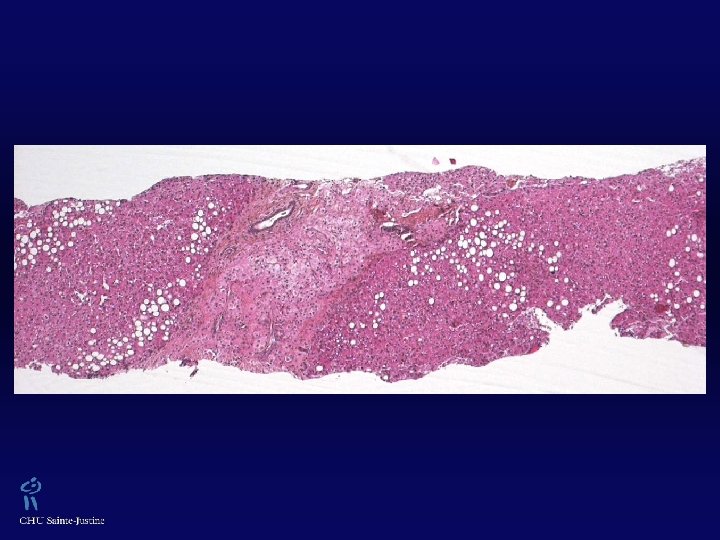

Histoséminaire Conjoint Université de Montréal / Université Mc. Gill 20 juin 2007 Anne-Laure Rougemont Dr Pierre Brochu CH-07 -02809

Histoire clinique w Fillette de 8 mois, caucasienne w Hépatosplénomégalie dès l’âge de 5 mois w 2 taches café-au-lait (bras et dos)

w Anémie et thrombocytopénie discrètes w Hypoalbuminémie, hypertriglycéridémie w Absence perturbation des tests hépatiques w Lésions hépatiques hypoéchogènes, US w CT-scan et IRM normaux w Péliose ? Hémangiomes ? → Traitement de Prednisone → Normalisation plaquettes et coagulation → Biopsie hépatique, mars et avril 2007